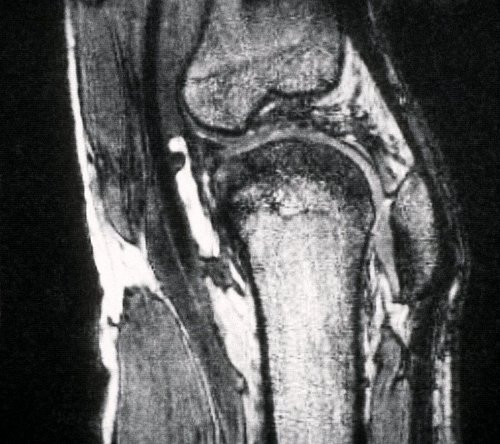

Bei den Knie- und Hüftspritzen geht es um Injektionen mit Hyaluronsäure, die fehlende Gelenkflüssigkeit ausgleichen soll. Diese Spritzen kosten pro Behandlungszyklus zwischen etwa 220 und 300 Euro. Je nach verwendetem Präparat können aber auch 500 Euro und mehr fällig werden. Dabei überwiegen bei diesen Spritzen mögliche Schäden den Nutzen laut Medizinischem Dienst deutlich. Dies gehe aus zahlreichen Studien hervor, mit denen diese Injektionen seit über 50 Jahren bewertet würden, so der Medizinische Dienst.

Dass die Spritzen gefragt sind, liegt an der weiten Verbreitung der Arthrose und dem Fehlen einer heilenden Therapie. Schätzungsweise ist in Deutschland jede sechste Person zwischen 60 und 80 Jahren von einer Kniegelenks- und jede und jeder Zehnte von einer Hüftgelenksarthrose betroffen - bei Über-80-Jährigen deutlich mehr. Im Gegensatz zur Hyaluronsäure-Injektion werden mehrere Behandlungen, die die Schmerzen lindern und die Beweglichkeit verbessern sollen, von den Kassen übernommen - bis hin zu Gelenkersatz bei schwerer Arthrose.